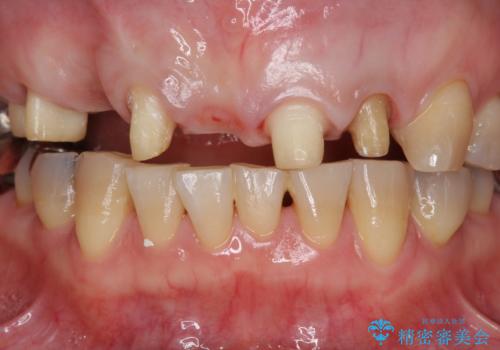

- 前歯を噛みしめにより失い、さらに犬歯もグラグラになり全く噛めなくなり改善を求めて来院されました。

過度な力がかかり周囲の骨に高度な吸収が見られた犬歯は抜歯し、機能・審美性の回復をより咬合力に対して抵抗力のあるブリッジ補綴にて対応します。

- 56円(仮歯・フルジルコニアクラウン×7)費用は治療当時の料金となります

ブリッジによる欠損補綴を行ったのち、ナイトガードを夜間装着していただき歯を守ります。